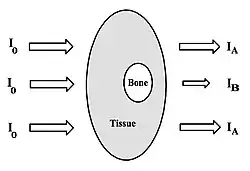

Subject contrast is developed mainly because of differences in the extent of photoelectric absorption in different tissues. Greater absorption occurs in bone relative to tissue, for instance, as we have previously described. This absorption completely removes X-ray photons from the beam so that what emerges from the patient and what is recorded by the image receptor are differences in X-ray attenuation.

where IA and IB are the transmitted X-ray intensities through two segments of tissue - see Figure 3.15, for an example. Our discussion here assumes for simplicity that the incident radiation consists of single energy photons, i.e. they are monoenergetic, and that only photoelectric effects occur in bone and tissue, i.e. no Compton nor coherent scattering occurs. We also assume an ideal imaging system, i.e. one that does not influence the contrast in any way - a gross over-simplification as we will see in the next chapter!

It is apparent from our earlier discussion about X-ray attenuation that both IA and IB are the result of exponential attenuation in the pure tissue and in the bone-plus-tissue regions, respectively. It is therefore apparent that the subject contrast depends on differences in thickness, density and/or effective atomic number of the anatomy being irradiated. The effective atomic numbers of bone and tissue are roughly 12.3 and 6.5, respectively, and the cubic dependence can give great contrast between these materials.

The contrast can therefore be re-expressed as:

where μa and μb are the linear attenuation coefficients of the tissue and bone, respectively and xb is the bone thickness. This equation indicates that the contrast is directly proportional to bone thickness with a constant of proportionality equal to the difference in linear attenuation coefficient between bone and tissue. It is apparent that contrast increases linearly with bone thickness in this idealized situation, which suggests that estimates of bone thickness could in principle be obtained from a contrast measurement. Scatter, as we will see, makes this virtually impossible, however.